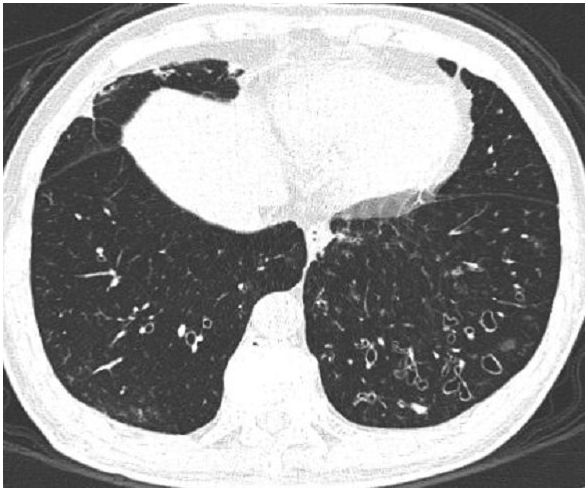

2. 40歲男性因高燒、胸痛和咳嗽來急診,胸部X光如圖所示,胸水中嗜中性白血球數> 1000/uL,抹片可見革蘭氏陰性菌,請問下列處置何者適宜? (A) 當胸水培養出來細菌時,即需插管引流 (B) 當胸水之pH < 7.20時,才需要插入胸管 (chest tube)引流 (C) 應儘早施行 decortication,才可預防發生纖維胸(fibrothorax) (D) 可反覆施行針抽胸水,即可防止出現纖維胸 (E) 應儘快施行胸管(chest tube)引流